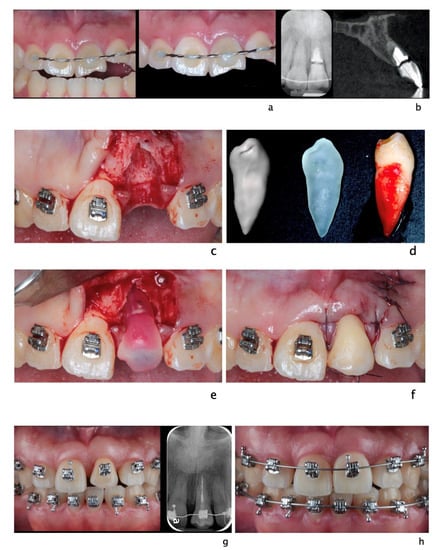

Figure 3.

A 20-year-old Asian male had #8 diagnosed with a root fractured due to sport related trauma (a). The tooth was endodontically treated, followed by healing with interposition of connective tissue (b). After healing was completed, a second sport injury involved the same tooth. The tooth mobility increased, and a periodontal lesion was diagnosed by elevated probing depth. The tooth was stabilized with orthodontic wire and patient was referred to periodontist for evaluation. Combined with malocclusion and anterior open-bite, the treatment plan was made as full-month orthodontics and auto-transplantation of #28. Tooth #8 and 28 were extracted (c,d) and a premolar replica was printed (d). After socket adjustment with the replica (e), tooth #28 was stabilized in place with sutures (f). After periodontal stabilization and verification of periodontal healing (g), the final restoration was delivered (h).